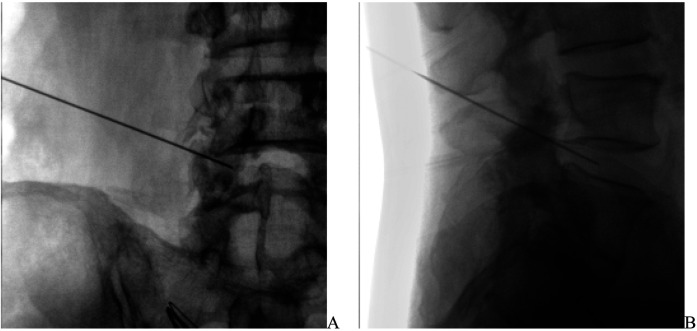

Methods: A total of 121 patients with LDH undergoing PIRFT treatment were selected, ranging in age from 35 to 65 years old, with no gender restrictions. Blood samples were collected in the morning after admission while fasting, and the absolute neutrophil and lymphocyte counts in the blood were detected using the enzyme-linked immunosorbent assay (ELISA) method to calculate the Neutrophil-to-Lymphocyte Ratio (NLR). Patients were divided into two groups according to the modified Macnab criteria: the Effective group (E group) and the Invalid group (I group). The Visual Analogue Scale (VAS), Oswestry Disability Index (ODI), and Japanese Orthopaedic Association (JOA) scores were used to assess the pain level and activity ability of the patients before treatment and at 90 days and 180 days post-treatment. The correlation between NLR and ODI, JOA scores was analyzed using rank correlation analysis, and the predictive value of NLR for the therapeutic effect of PIRFT was analyzed using the Receiver Operating Characteristic (ROC) curve.